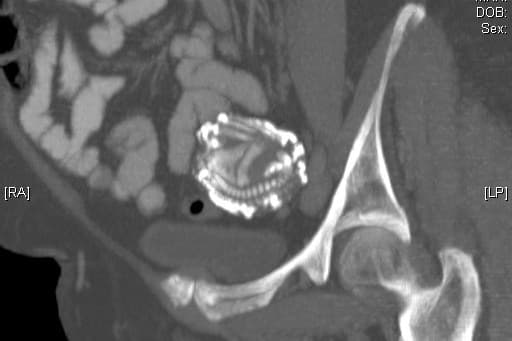

Los bebés de piedra se forman a partir de una condición llamada litopedia, la cual se produce con un embarazo extrauterino o ectópico, donde el feto muere y se calcifica.

La formación de un litopedión depende de varios factores. Primero ocurre el embarazo abdominal y el feto empieza a crecer.

El feto debe sobrevivir por más de 12 semanas, pero no es posible que viva fuera del útero. Al morir, el feto es demasiado grande para ser absorbido por el organismo de la mujer, por lo que se queda incrustado en el abdomen.

Si no hay síntomas ni se detecta el embarazo ectópico, el feto puede seguir creciendo hasta la semana 14, iniciando un proceso de deshidratación de tejidos y calcificación.

El sistema inmunológico de la mujer embarazada reconoce al feto como una amenaza y protege al organismo de una posible infección, revistiendo al feto con calcio.

El cuerpo necesita de mucho tiempo para acumular suficientes depósitos de calcio y convertir al feto "en piedra". Es por ello que pueden permanecer décadas dentro de la mujer sin ser detectados.